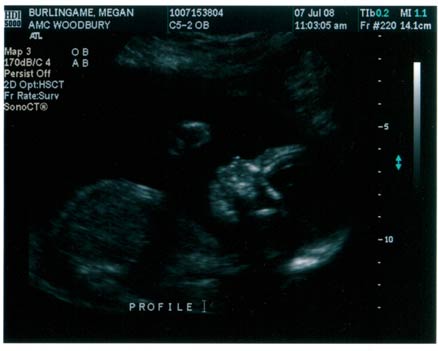

So, we have a funny story from the ultrasound yesterday and it was also captured on camera. At the ultrasound each time the technician would press the camera a little harder on my stomach our little boy would punch or kick back – EVERY SINGLE TIME!!! By the time we were finished with the ultrasound I felt like I had been through the wringer – inside and out. It took a few hours for everything to get back to normal. We are so thrilled with the images we received and hope to see better ones on Friday when we have our second ultrasound in 3-D.

If you look closely at the picture you can see him punching upwards. I felt the punch as she took the picture, it was really cool.